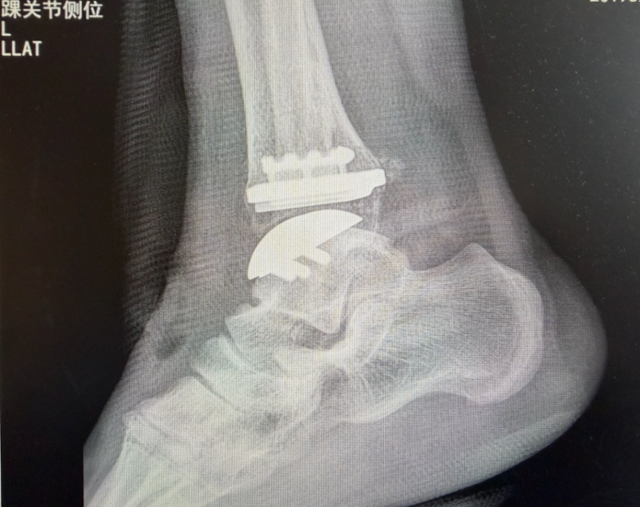

手术前后影像对比

手术黑科技:3D打印“量身定制”新关节

传统的人工关节就像“均码鞋”,不一定合脚。这次医生用了最新技术——3D打印人工关节,其核心优势在于:

个体化精准匹配:

基于张叔踝关节的精细CT数据,通过计算机三维重建与设计,为他“量身定制”了与自身骨骼形态高度吻合的假体。可保证假体与宿主骨骼实现最大化接触与匹配,为长期稳定奠定了力学基础。

长久生物性固定:

假体采用具有生物相容性的多孔金属材料(如钽或钛合金)打印而成。这种仿生结构能允许人体骨骼组织长久入孔隙之中,实现假体与骨骼之间牢固的生物性整合(即“骨长入”),从而极大提升了假体的长期稳定性与使用寿命。